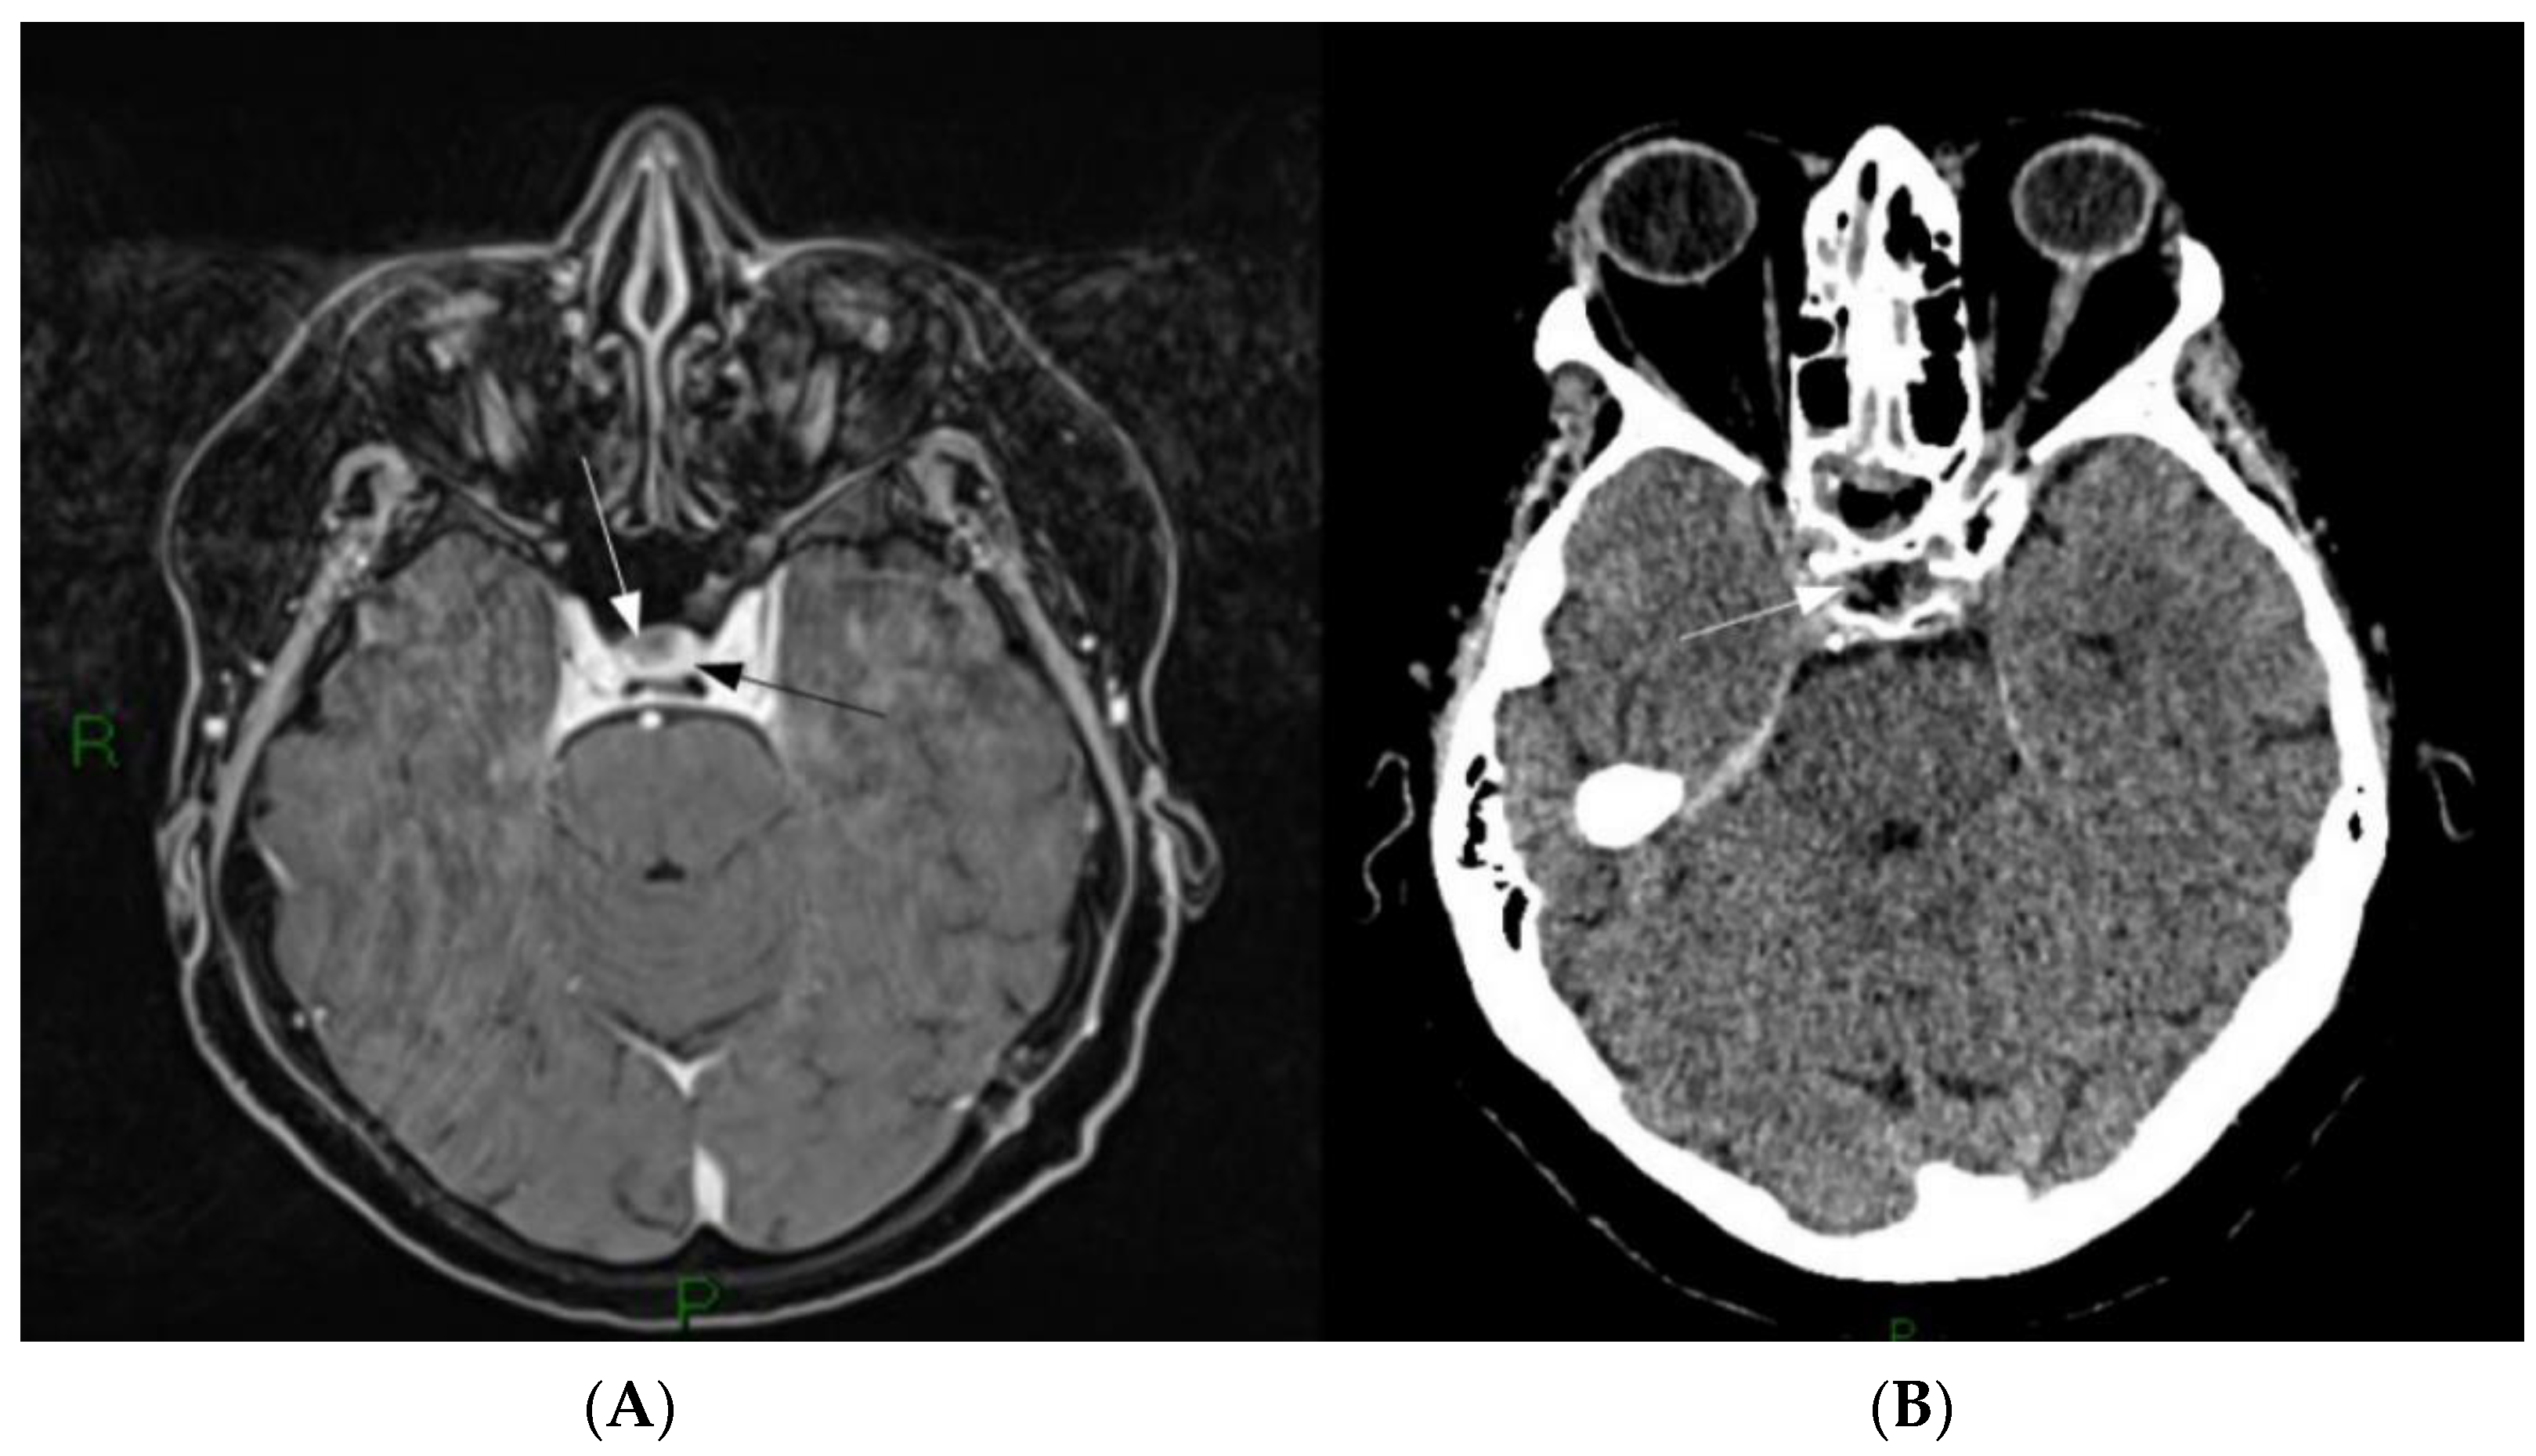

3.3. Fluorescein